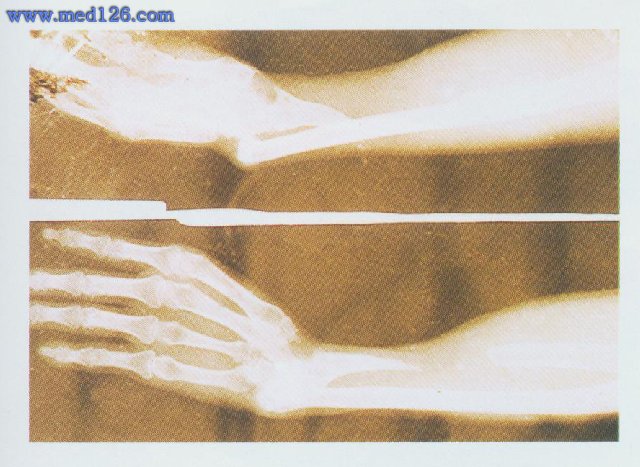

X线片示桡骨缺损范围(图2)

图2